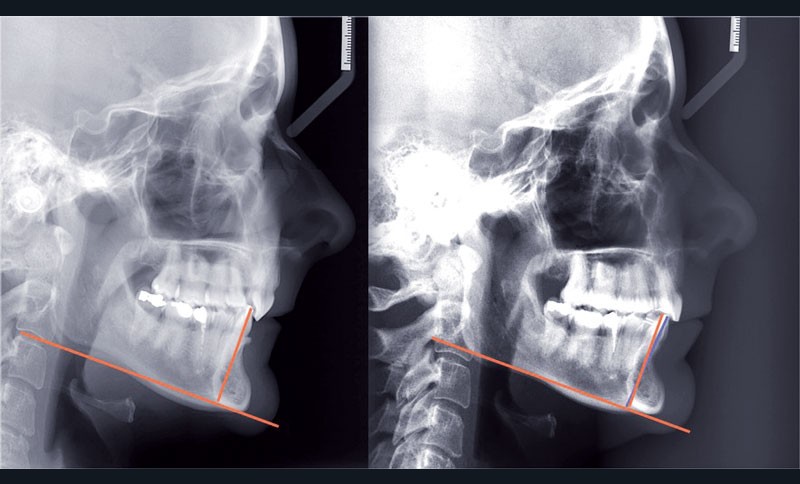

Cas n° 2

Nous lui avons donc proposé un traitement d’alignement avec maintien des 14 et 24 en position de 13 et 23 et optimisation du torque pour favoriser un développement des arcades et chercher à améliorer le sourire et le soutien labial.

Le projet thérapeutique